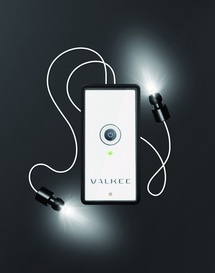

Fuente: Valkee.

Por esta razón, los científicos han desarrollado unos auriculares que proyectan luz a través de los canales auditivos, para hacerla llegar hasta unas proteínas fotosensibles presentes en la superficie del cerebro. Los resultados obtenidos por el momento en el tratamiento del TAD con este sistema han resultado prometedores.

El dispositivo ha sido desarrollado por un fisiólogo de la Universidad de Oulu llamado Juuso Nissilä, después de que éste realizara una investigación en la que se descubrieron proteínas fotosensibles en la superficie de los cerebros de animales.

Por esta razón, los científicos han desarrollado unos auriculares que proyectan luz a través de los canales auditivos, para hacerla llegar hasta unas proteínas fotosensibles presentes en la superficie del cerebro. Los resultados obtenidos por el momento en el tratamiento del TAD con este sistema han resultado prometedores.

El dispositivo ha sido desarrollado por un fisiólogo de la Universidad de Oulu llamado Juuso Nissilä, después de que éste realizara una investigación en la que se descubrieron proteínas fotosensibles en la superficie de los cerebros de animales.

El aparato creado por Valkee contiene en cada auricular un White LED que produce luz en longitudes de onda cercanas a las de la luz solar. Fuente: Valkee.

Para desarrollar el casco auricular de luz, Nissilä ha co-fundado una compañía bautizada como Valkee. El aparato creado contiene en cada auricular un White LED (diodo orgánico que emite luz blanca más brillante) que produce luz en longitudes de onda cercanas a las de la luz solar. Los investigadores de Valkee han publicado recientemente los resultados de su primera prueba clínica con este sistema en la revista Medical Hypothesis.

Para desarrollar el casco auricular de luz, Nissilä ha co-fundado una compañía bautizada como Valkee. El aparato creado contiene en cada auricular un White LED (diodo orgánico que emite luz blanca más brillante) que produce luz en longitudes de onda cercanas a las de la luz solar. Los investigadores de Valkee han publicado recientemente los resultados de su primera prueba clínica con este sistema en la revista Medical Hypothesis.